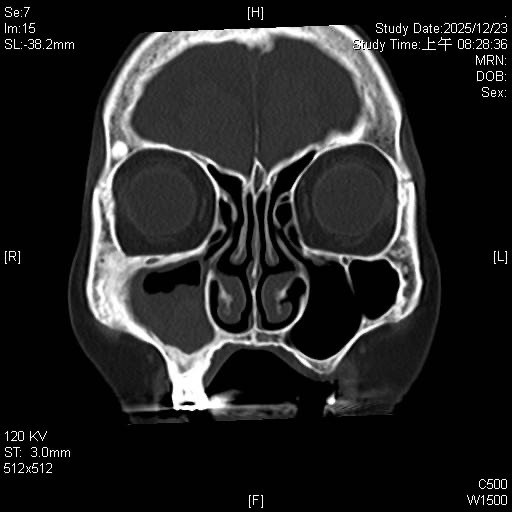

〔記者黃美珠/新竹報導〕一名90歲阿嬤多年深受慢性鼻竇炎和嚴重鼻涕倒流所苦,睡眠受影響,生活品質也大打折扣。因為她年事已高擔心全身麻醉手術風險高,所以先前求診過的醫院多不建議手術根治。東元綜合醫院耳鼻喉科醫師詹健暘評估改用局部麻醉的「鼻竇內視鏡微創手術」,移除鼻竇內的黴菌塊(Fungal Ball),才讓她的長年宿疾終獲緩解。

詹健暘說,阿嬤是慢性鼻竇炎,伴隨黴菌性鼻竇炎(fungal sinusitis)患者,這類疾病因台灣氣候潮濕而很常見,黴菌球(塊)因常堆積在單側上頜竇,在鼻竇內不斷堆積成團塊,屬於非侵襲性的黴菌感染,典型症狀就是單側或局部鼻竇阻塞、鼻涕倒流,甚至併發頭痛。